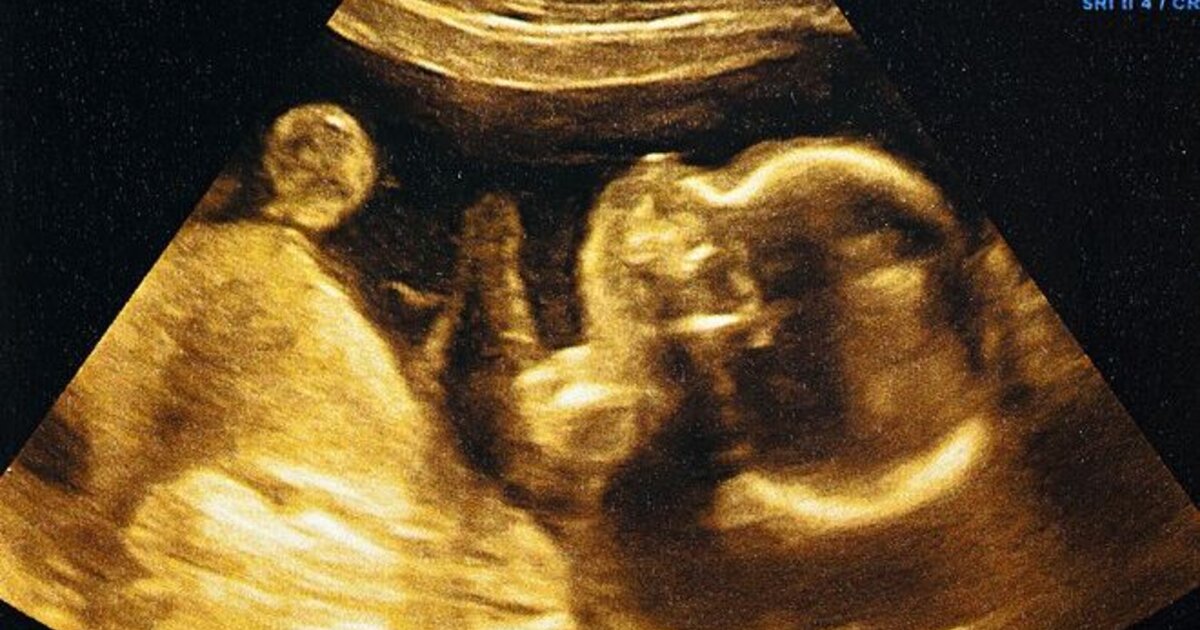

Για να διερευνήσει εάν τα έμβρυα διαφοροποιούν συγκεκριμένες γεύσεις, η ομάδα εξέτασε υπερηχογράφημα από σχεδόν 70 έγκυες γυναίκες, ηλικίας 18 έως 40 ετών από τη βορειοανατολική Αγγλία, οι οποίες χωρίστηκαν σε δύο ομάδες. Ζητήθηκε από τη μία ομάδα να πάρει μια κάψουλα kale σε σκόνη 20 λεπτά πριν από τον υπερηχογράφημα και από την άλλη ζητήθηκε να πάρει μια κάψουλα καρότου. Η κατανάλωση λαχανικών από τις μητέρες δεν διέφερε μεταξύ της ομάδας του kale και του καρότου.

Στη συνέχεια, η ομάδα πραγματοποίησε ανάλυση καρέ προς καρέ της συχνότητας μιας σειράς διαφορετικών κινήσεων του προσώπου των εμβρύων, συμπεριλαμβανομένων συνδυασμών που έμοιαζαν με γέλιο ή κλάμα. Και αυτό που παρατήρησαν ήταν εντυπωσιακό.

Μεταξύ των αποτελεσμάτων, η ομάδα βρήκε ότι τα έμβρυα έδειχναν μια έκφραση κλάματος περίπου δύο φορές πιο συχνά όταν η μητέρα κατανάλωνε μια κάψουλα λαχανίδας σε σύγκριση με μια κάψουλα καρότου ή και χωρίς κάψουλα. Ωστόσο, όταν η μητέρα κατανάλωνε μια κάψουλα καρότου, τα έμβρυα υιοθέτησαν μια έκφραση γέλιου περίπου δύο φορές πιο συχνά από ό,τι όταν η μητέρα κατάπιε είτε μια κάψουλα λαχανίδας είτε καμία κάψουλα.